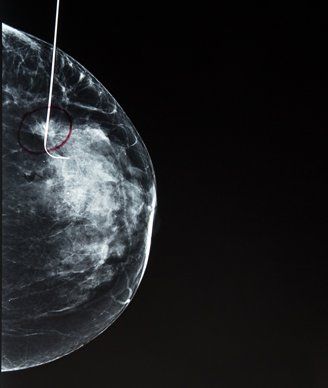

Image © David Litman / shutterstock.com